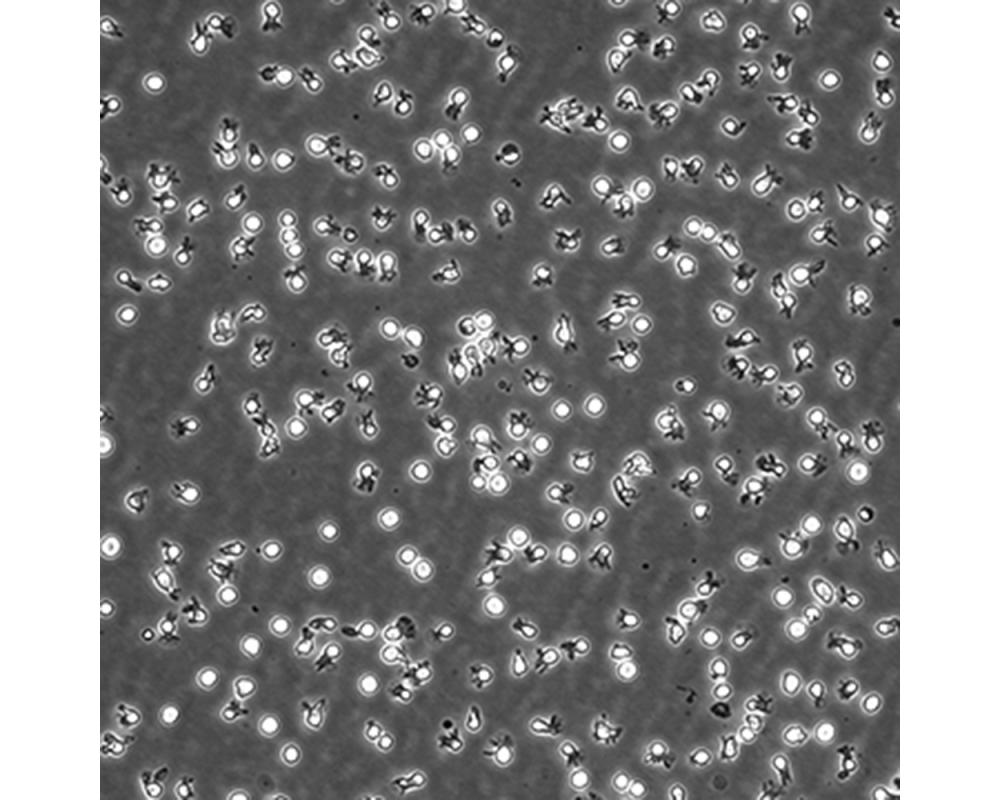

中文名稱 人彌漫大B細(xì)胞淋巴瘤細(xì)胞

生長(zhǎng)特性 懸浮